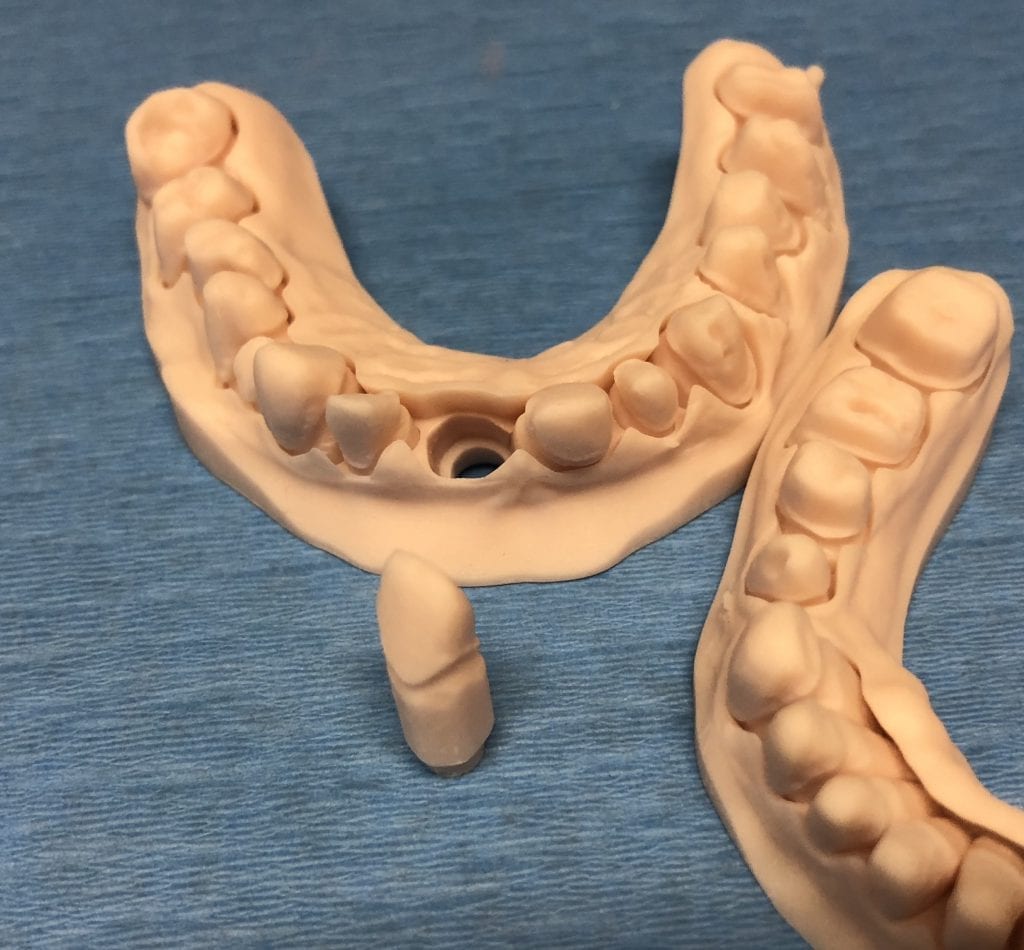

The case was designed by CADENT BESSA, and the models were printed by Burbank Dental Lab with Carbon Printers. There restorations were milled and cut back and layered by Burbank Dental Lab

IMAGES OF PRINTED MODELS